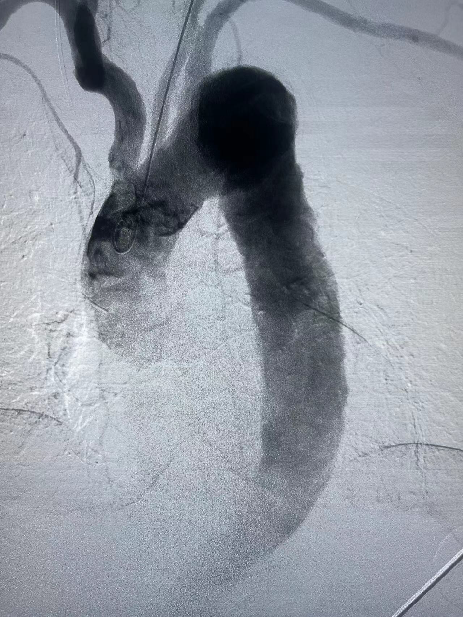

患者男性,51岁,主动脉夹层,通过Futhrough系统完成左锁骨下动脉(LSA)原位开窗重建。术中使用可调弯鞘(Fustar)和破膜系统,DSA显示破膜即刻成功,术后分支通畅,无并发症。

穿刺破膜

球囊后扩

术后造影